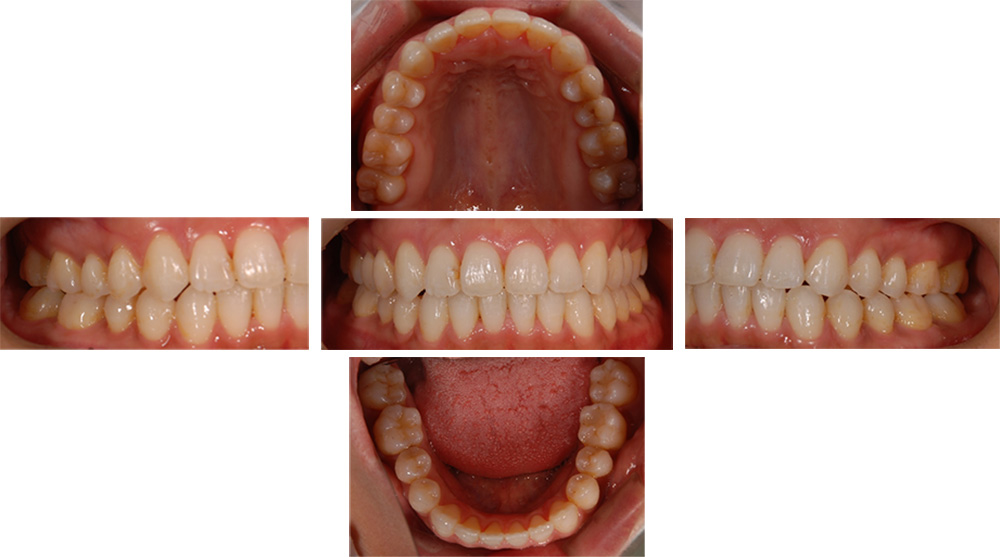

| 治療回数 | 36回 |

|---|---|

| 年齢・性別 | 30代 女性 |

| 治療期間 | 1年10ヶ月 |

| 治療費用 | 990,000円(税込) |

| 調整費 | 6,600円×来院毎(税込) ※2年目から |